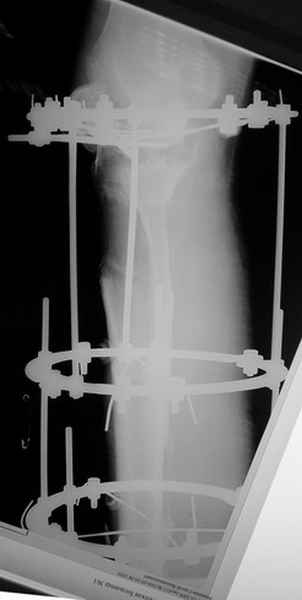

Пациент В. 53 лет, травма в феврале 2009. ДЗ. Открытый оскольчатый перелом нижней трети голени. При боли поступлении выполено ПХО, аппарат Илизарова. В последующем проводили ВХО, резекция костных отломков, укорочение 6 см, рана зажила. Была выполнена остеотомия большеберцовой кости в проксимальном отделе, резекция. Производилось тракция. На последних рентгенограммах выявлено, что одновременно с "выращиванием" регенерата произошло низведение надколенника на длину выращенного регенерата. Клинически: активное разгибание сохранено, объем движений в колене 180-110 градусов. Черными стрелками обозначен верхний край надколенника с одной и с другой стороны. Красная стрелка обозначает пальпируемую связку надколенника. Причина - остеотомия выше места прикрепления связки надколенника. Вопрос: была ли у кого подобная ситуация? Что делать? При первом обдумывании приходит решение: отсечение места прикрепления связки надколенника с костным блоком, перемещение на "правильное" место, укорочение сухожилия четырехглавой мышцы.

По снимкам - плотность регенерата хорошая, сложностей с фиксацией в него костного "основания" быть не должно.

К сожалению, подобное осложнение "нет-нет да и возникает" при удлинении, коррекции деформации голени. В англоязычной литературе оно описано как "patella baja". Один из вариантов лечения - проксимальное перемещение надколенника приемами чрескостного остеосинтеза.

Я бы уменьшил диастаз между фрагментами сантиметра на два. Судя по снимкам, регенерат это может позволить.